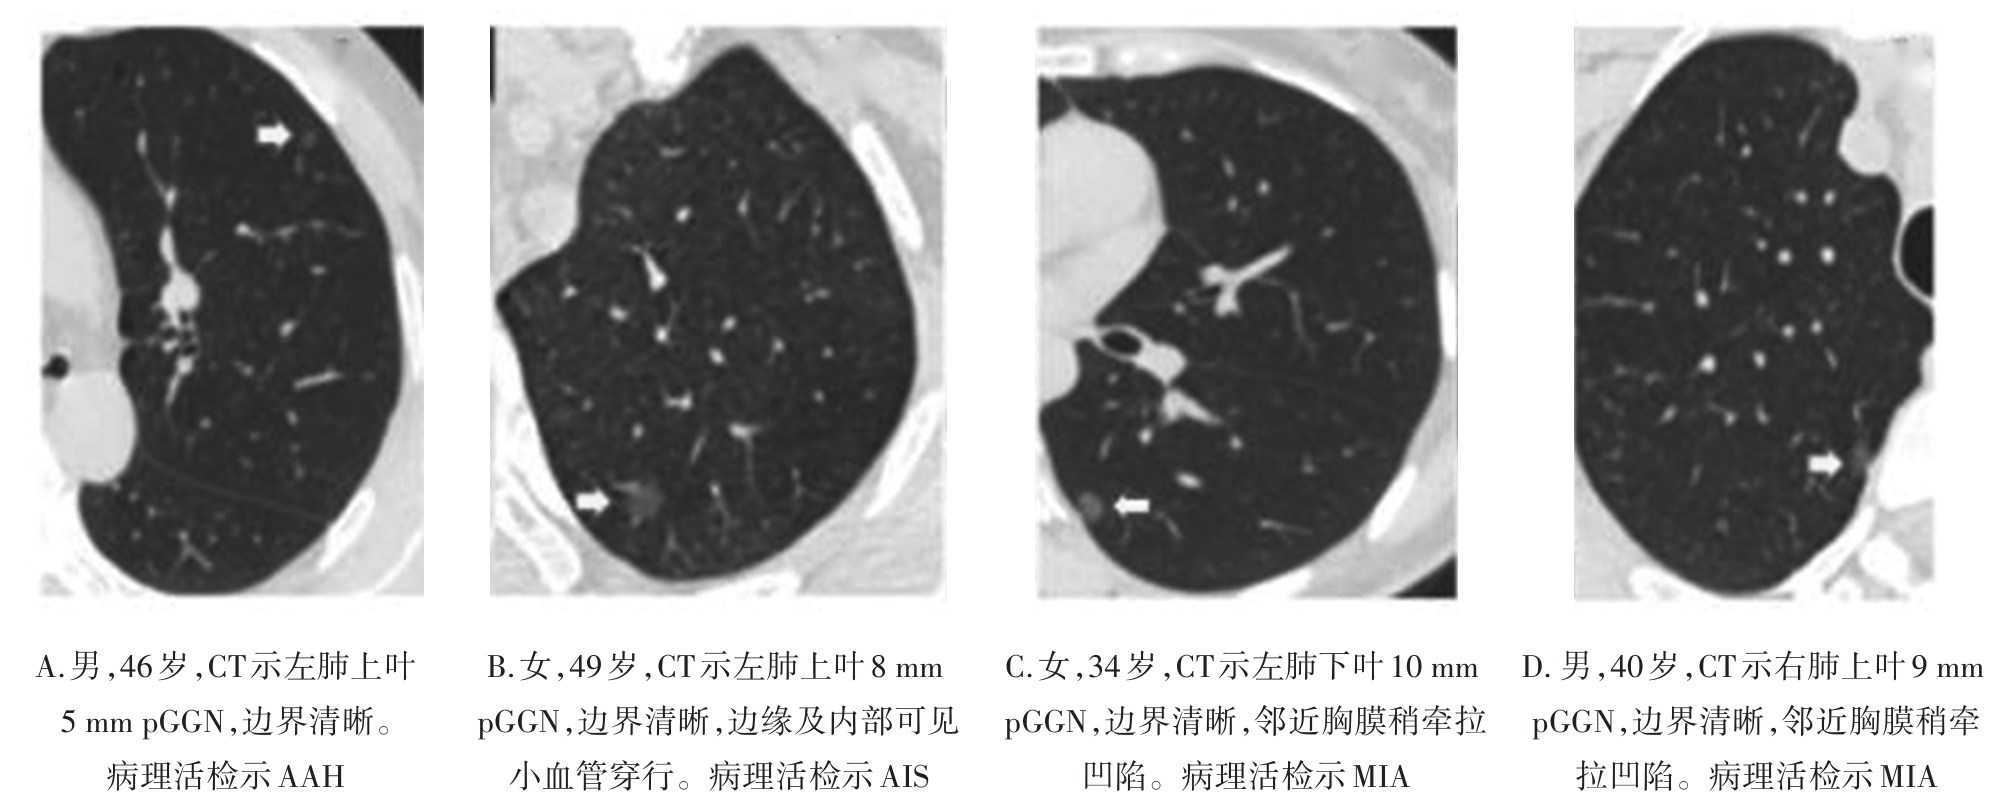

• 纯磨玻璃结节肺腺癌CT征象与其浸润程度的相关性分析及预测模型构建

2023, 48(4):423-429. DOI: 10.13406/j.cnki.cyxb.003200

摘要 (138) HTML (44) PDF 1.10 M (286) 评论 (0) 收藏

摘要:目的 探究纯磨玻璃结节(pure ground-glass nodule,pGGN)肺腺癌计算机断层扫描(computed tomography,CT)征象与其浸润程度的相关性,建立CT征象与浸润程度的预测模型。方法 回顾性分析424例经手术切除、病理活检证实且胸部CT表现为pGGN的肺腺癌患者临床资料及CT征象,根据病理活检结果分为非典型腺瘤样增生、原位腺癌、微浸润腺癌和浸润性腺癌4组,对组间差异采用卡方检验或Fisher确切概率法进行统计分析。对有统计学意义的结果,使用怀卡托智能分析环境(Waikato environment for knowledge analysis,WeKa)中的6种学习算法进行预测模型构建,并验证准确性,挑选出最适用于本研究的预测模型。结果 4组间在结节直径、结节密度值上的差异具有统计学意义(P<0.001),对应的直径平均值分别为6.90、8.65、10.71、14.56 mm,对应的密度平均值分别为-633.16、-543.04、-401.03、-322.94 HU,随着病灶的浸润程度加重,结节的直径及密度值呈现明显的上升趋势。4组间在结节边界、分叶、毛刺、血管穿行、胸膜凹陷、空气支气管征、空泡征等的差异具有统计学意义(P<0.05),而结节的生长位置,年龄、吸烟史、直系亲属肺癌家族史等差异无统计学意义(P>0.05)。随机森林算法所构建的模型预测准确率为76.42%~79.72%,Kappa系数为0.597~0.670,受试者工作特征(receiver operating characteristic,ROC)曲线下面积均大于0.9,在误差指标中表现最优,是最适合于本研究的预测模型。结论 pGGN的不同CT征象与其浸润程度密切相关,可以用于建立预测模型。基于随机森林算法所建模型,在有创干预前早期快速识别pGGN浸润程度的平均准确率为78.07%,准确度最高,对肺癌预测具有潜在应用价值。

• 0+1

• 1+1

• 2+1

• 3+1

• 4+1